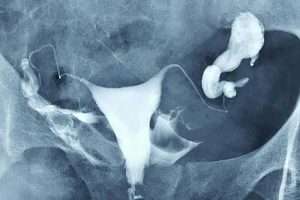

Tüplerde Sıvı Birikmesi